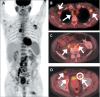

Results: We evaluated 79 patients, of whom 38 (48.1%) had pathology-proven inguinal LN metastasis. Certain imaging aspects- short-axis diameter, prostate-specific membrane antigen uptake on positron-emission tomography, membranous urethra involvement by the tumor, extra-inguinal lymphadenopathy, and distant metastases-were associated with pathology-proven inguinal LN metastases (p < 0.01 for all). Associations with long-axis diameter, fatty hilum, laterality, and uptake of other tracers on positronemission tomography were not significant (p = 0.09-1.00). The patients with metastatic inguinal LNs had higher prostate-specific antigen levels and more commonly had castration-resistant PCa (p < 0.01), whereas age, histological grade, and treatment type were not significant factors (p = 0.07-0.37). None of the patients had inguinal LN metastasis in the absence of locally advanced disease with membranous urethra involvement or distant metastasis.

Conclusion: Several imaging, clinical, and pathology features are associated with inguinal LN metastases in patients with PCa. Isolated metastasis to inguinal LNs is extremely rare and unlikely to occur in the absence of high-risk imaging, clinical, or pathology features.